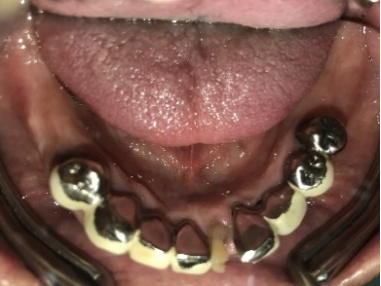

女性Mさん 40代(インプラント)

下、左右歯がないところに歯を入れたい。

治療内容

右下に2本、左下に1本インプラントを入れました。

所感

下顎左右奥の歯がないところに、インプラント治療を希望されて来院されました。X-Guideを使用し埋入しました。治療後「左右の奥歯でしっかり噛めてうれしいです。」と、とても喜んでくださいました。

Before

After